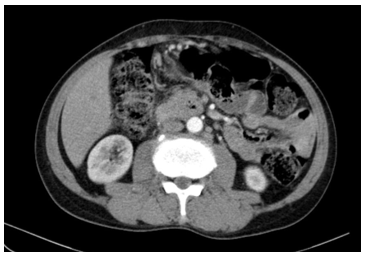

- CT ổ bụng: Hình ảnh vài nốt ngấm thuốc nhu mô gan. Vài hạch dọc động mạch chủ, kích thước lớn nhất 17x10mm

Hình 1. Hình ảnh cắt lớp vi tính ổ bụng trước điều trị (hạch dọc động mạch chủ)